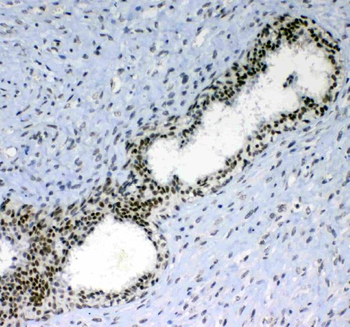

10 μg, 100 μg - Anti-S100 alpha 6/S100A6 Antibody [orb315184]

FC, ICC, IF, IHC, WB

Human, Mouse, Rat

Rabbit

Polyclonal

Unconjugated

10 μg, 100 μg - Anti-HSD11B2 Antibody [orb316541]